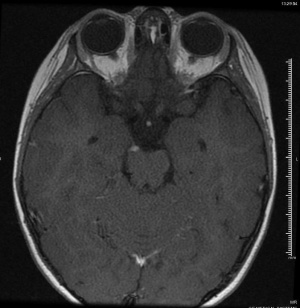

Imaging in the form of MRI or CT at a minimum should be performed to rule out orbital, parasellar, or posterior fossa lesions.[4][6] Mark et al were the first to describe oculomotor nerve enhancement and thickening on MRI in a patient with OM/RPON,[25] and a follow-up study confirmed the finding in 6 patients with OM/RPON.[17] Since then, numerous other studies have confirmed reversible cranial nerve enhancement in cases not just involving the oculomotor nerve, but the abducens and trochlear nerves as well.[19][26][27][28] While reversible focal enhancement and thickening of the cisternal portion of the oculomotor nerve can be seen, 25-81% of cases may have a normal MRI in the acute phase.[6] Enhancement and thickening of the third nerve usually disappear gradually as the patient’s symptoms subside, suggesting that the clinical symptoms may be associated with this radiologic finding.[17] The time it takes for MRI enhancement to disappear is variable: Mark et al reported near complete resolution of enhancement on follow-up studies 7-9 weeks after an attack,[25] while Prats et al reported resolution after a much longer period of 2-4 years.[29]